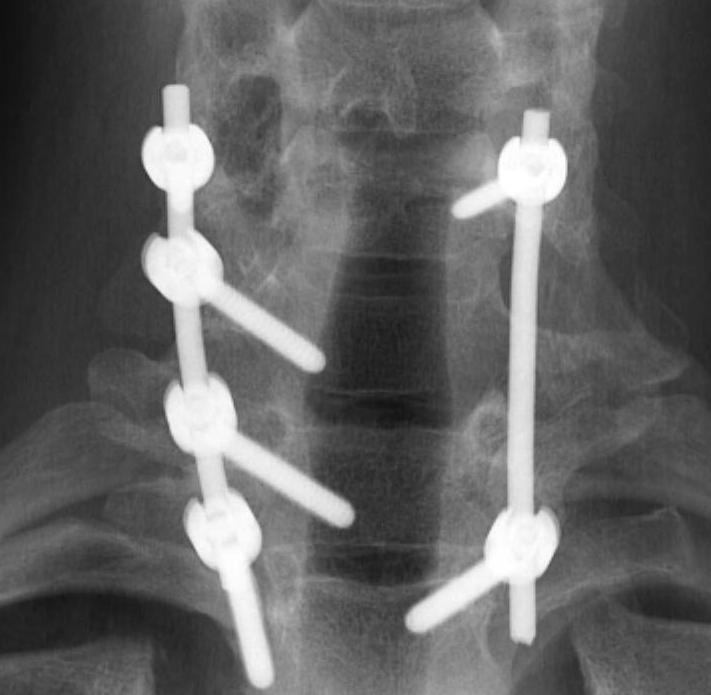

Osteoblastoma Exision and Fusion0001Osteoblastoma Exision and Fusion0002

Wide excision +/- posterior fusion

Can recur

- life long follow up